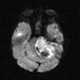

Teratoid tumor

An atypical teratoid rhabdoid tumor (AT/RT) is a rare tumor usually diagnosed in childhood. Although usually a brain tumor, AT/RT can occur anywhere in the central nervous system (CNS), including the spinal cord. [Source: Wikipedia ]